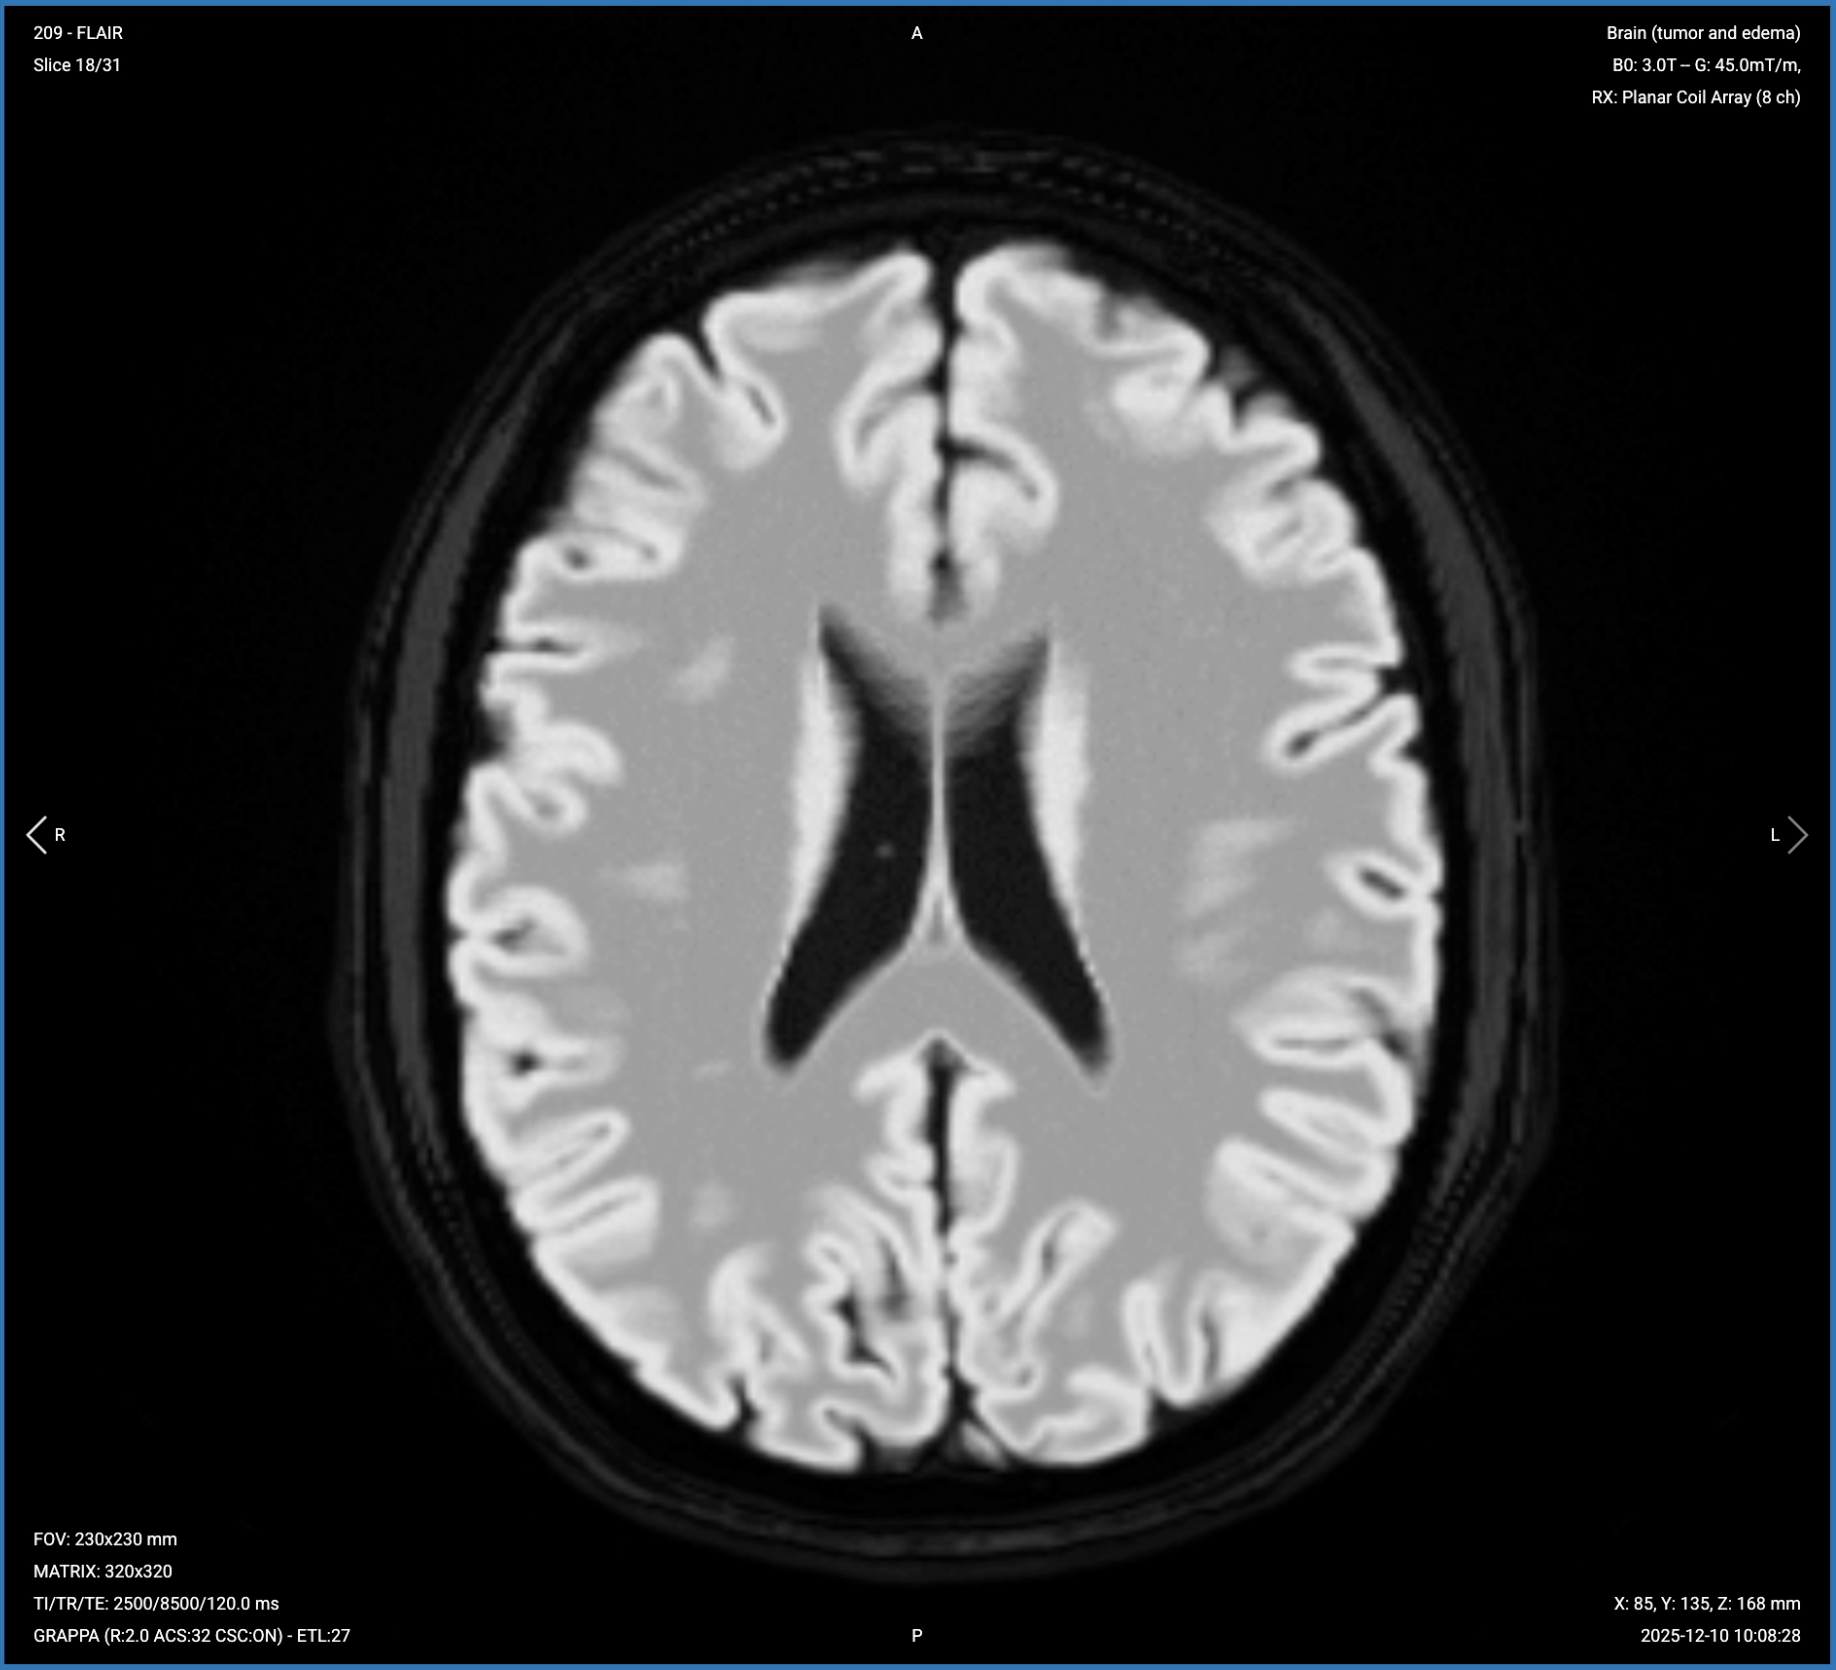

3. Planning Axial T2 FLAIR Fat-Sat

✅ Correct Planning:

Correct Planning Axial T2 FLAIR Fat-Sat

Planning Instructions:

• Copy the slice geometry and planning from the axial T2 TSE sequence.

• Keep the same slice angulation, coverage, and positioning to ensure images of different contrasts can be clearly compared.

T2 FLAIR Fat-Sat – Best for Infiltrative Margins and Non-Enhancing Tumor Extent

T2 FLAIR (Fluid Attenuated Inversion Recovery) suppresses CSF signal while preserving sensitivity to pathological water. This makes tumor-related abnormalities highly visible, especially near ventricles where bright CSF on standard T2 could obscure lesions.

In brain tumor imaging, FLAIR is critical for detecting infiltrative margins and non-enhancing tumor extension. If the signal doesn't suppress, it's tumor with different timing than CSF, helping us see areas beyond what T2 and post-contrast T1 show. It gives us an intuition of the periventricular situation, whether the tumor infiltrates into the ventricle or not. FLAIR also highlights lesions by suppressing the bright CSF background.

We acquire this sequence in the axial plane to match the T2 TSE, allowing direct comparison between sequences and assessment of infiltrative extent in the same anatomical plane.

Axial T2 FLAIR Fat-Sat of the Brain – Correct Image Example:

Axial T2 FLAIR Fat-Sat of the Brain – Correct Image Example

Things to Look for in Axial T2 FLAIR Fat-Sat:

• Non-enhancing tumor extent beyond the enhancing margins seen on post-contrast images.

• Infiltrative margins extending into white matter.

• Tumor-related edema clearly visible against dark CSF background.

• Periventricular involvement – check if tumor infiltrates ventricles.

• CSF suppression quality – CSF should appear uniformly dark.